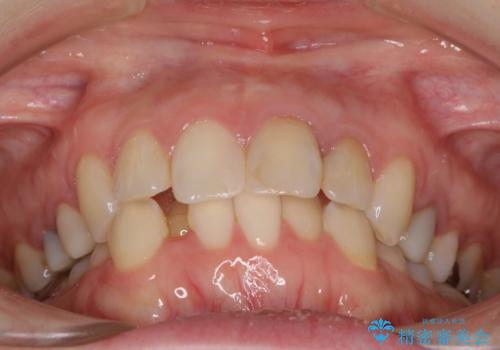

【モニター】前歯のデコボコと奥歯の虫歯 インビザライン治療と奥歯のセラミック治療

- 前歯のデコボコと奥歯の虫歯を気にして来院された患者様です。

主に下顎歯列全体の後方移動とIPR(歯と歯の間を削る)によってデコボコが解消するように設計し、インビザラインにより治療を行うこととしました。

矯正治療後半に下顎左右奥歯をセラミッククラウンにて補綴し、その後インビザラインによる歯列の仕上げを行うこととしました。

下顎前歯の叢生が速やかに改善されたため、1年3か月で治療を終えることができました。

下顎前歯は後戻りを起こしやすいため、舌側を細いワイヤーで固定することで後戻り対策を行っています。